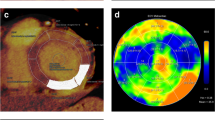

ROC curve analysis (Fig. 2)

Receiver operating characteristic (ROC) curves to detect the optimal threshold of MIC on 5-minute acquisition. AUC values were 0.53, 0.72, 0.84 and 0.99, respectively, for arterial MIC (blue line), arterial iodine ratio (green line), 5-minute MIC (yellow line) and 5-minute iodine ratio (purple line)

Patients with CA formed the positive case group and CH patients were considered as negative cases. Control patients were excluded so as to reflect clinical practice. The areas under curve (AUCs) of arterial and 5-minute MIC for diagnosed CA patients as opposed to CH patients were 0.53 (95% CI: 0.32–0.75, p = 0.7), and 0.84 (95% CI: 0.72–0.99, p < 0.005), respectively. With a cut-off of 2.2 mg/mL, the sensitivity and specificity of 5-minute MIC to diagnose CA were 82% and 75%, respectively. Higher performances were noticed for iodine ratios: the AUCs of arterial and 5-minute iodine ratio were 0.72 (95% CI: 0.53–0.91, p < 0.05) and 0.99 (95% CI: 0.96–1.02, p < 0.001), respectively. With a threshold of 0.65, the sensitivity and specificity of 5-minute iodine ratio were 100% and 92%, respectively. For ECV, a value of 0.45 resulted in 100% discrimination between CA and CH patients.